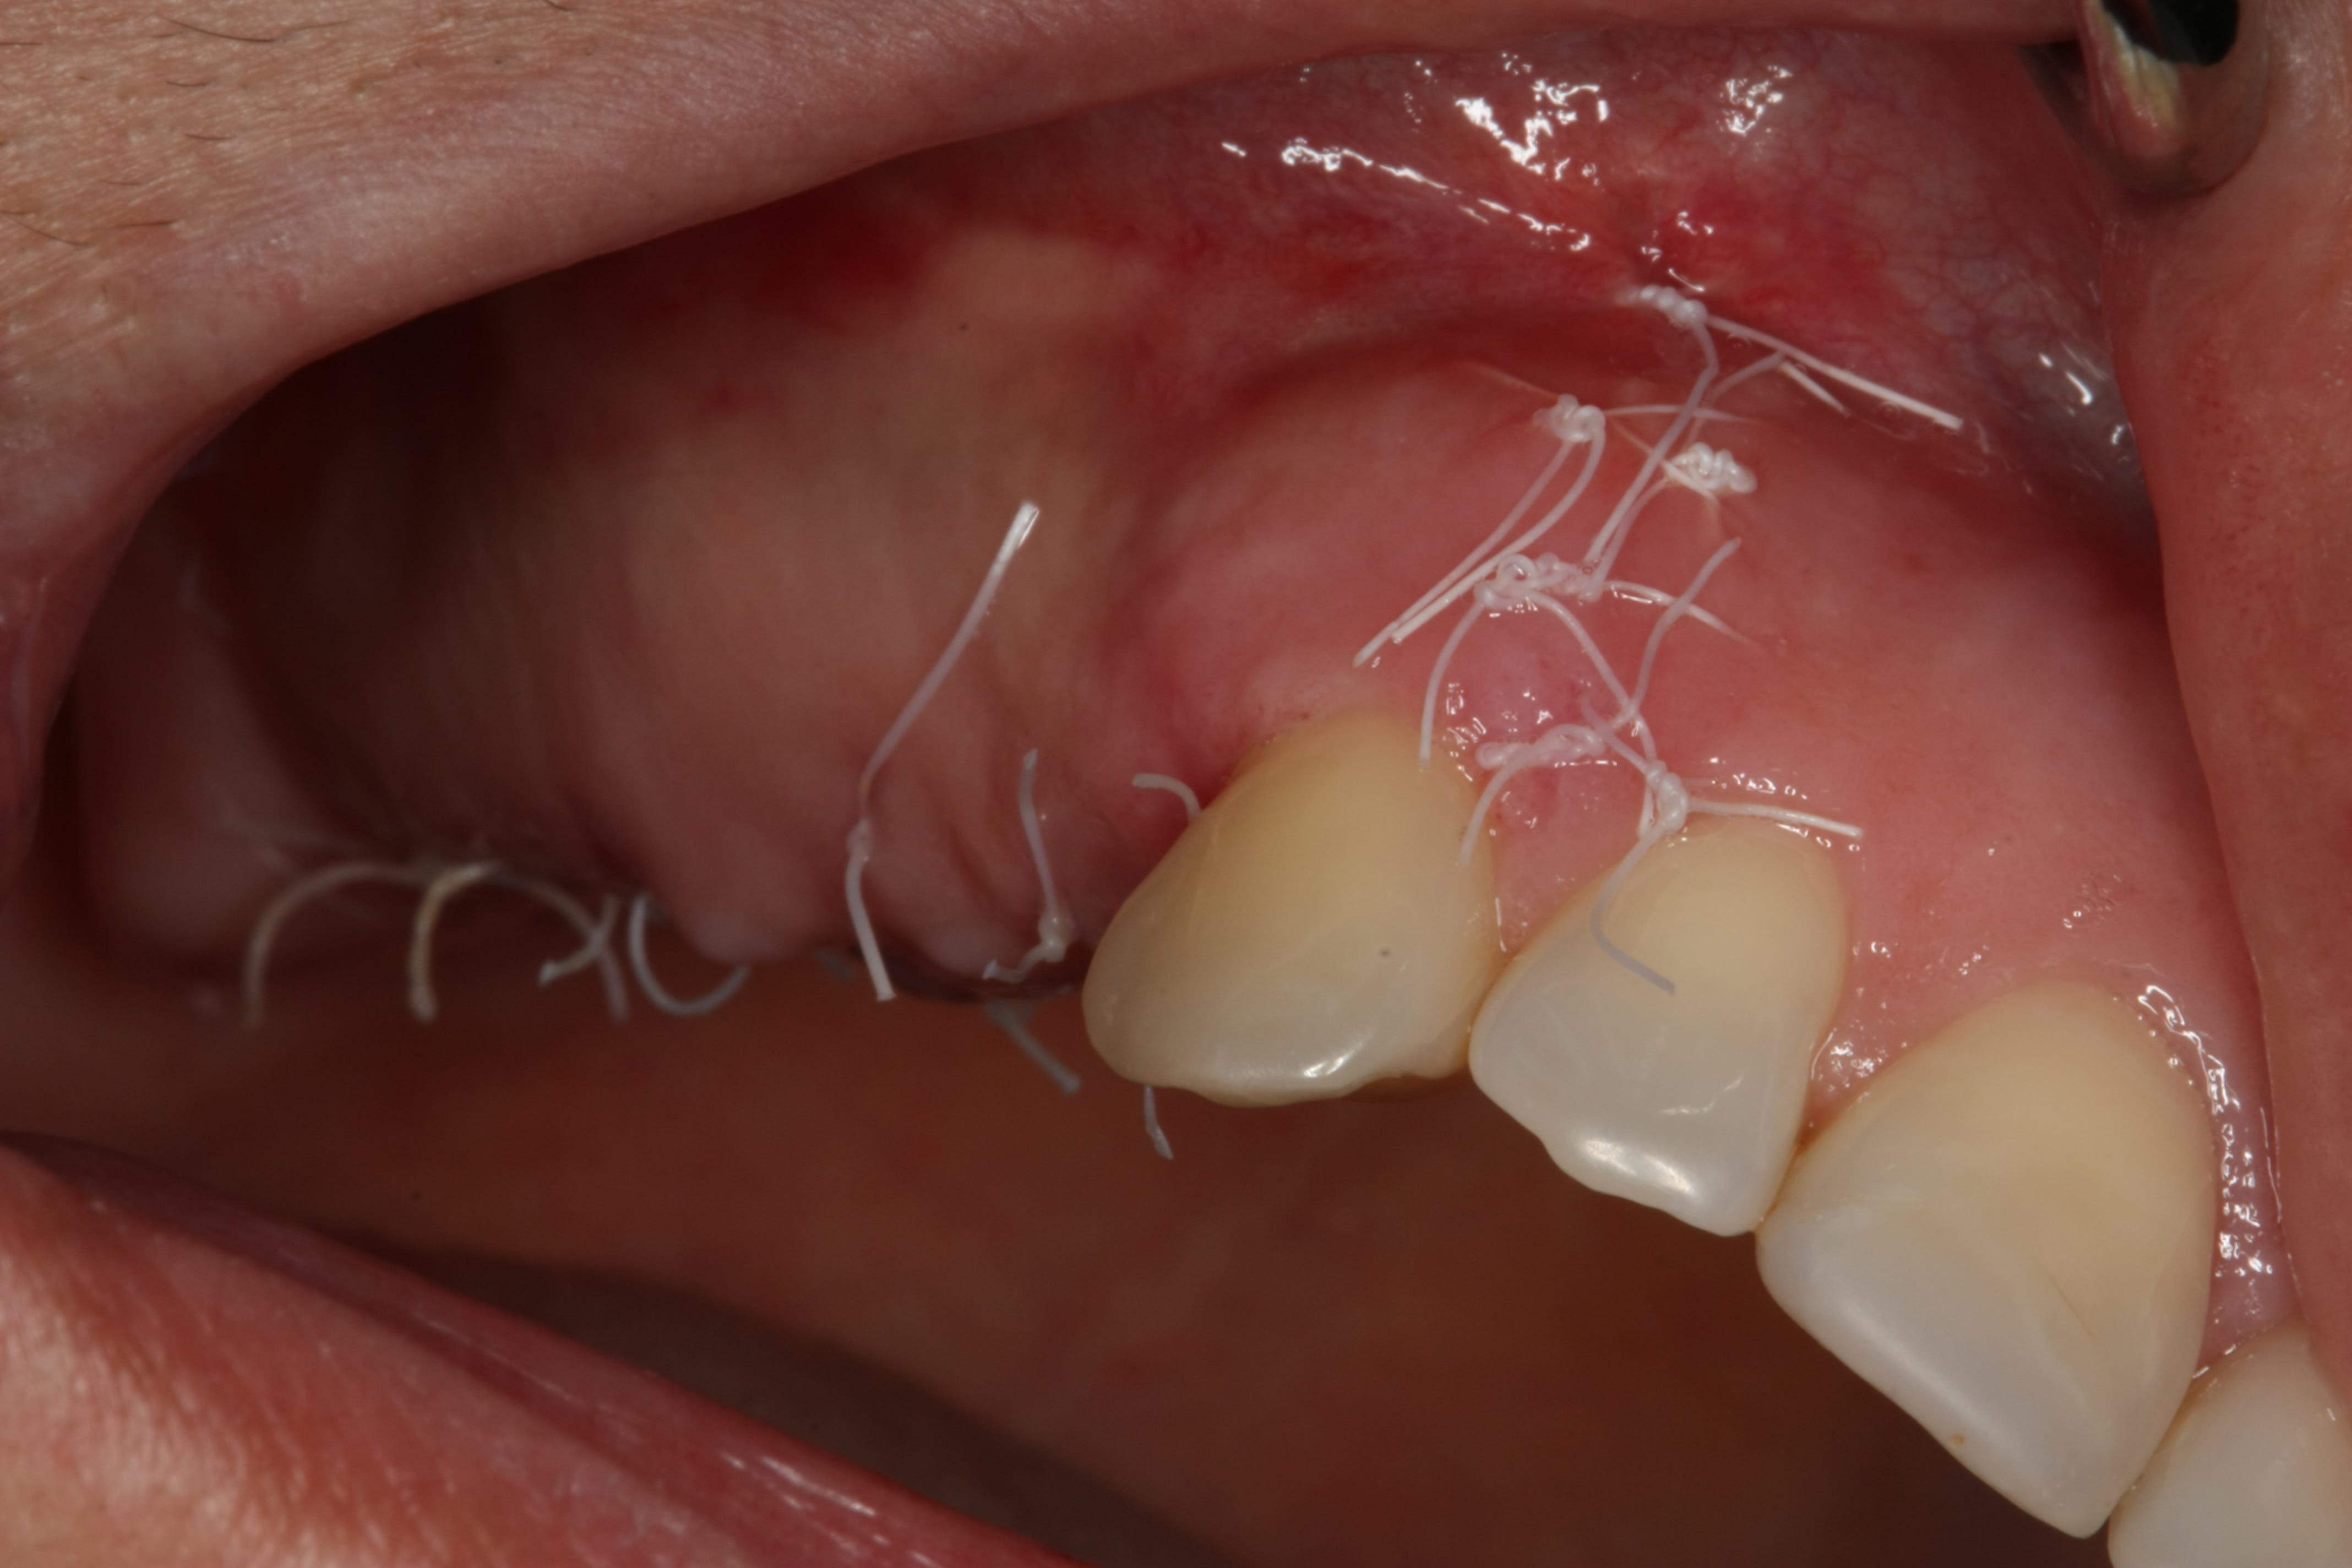

2e temps 5 mois après pose

Empreinte 1 mois après